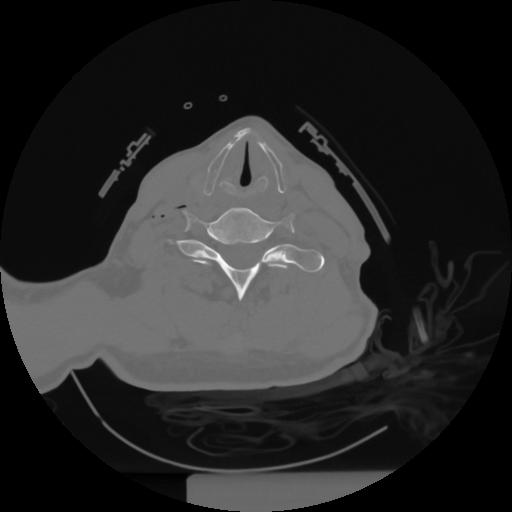

12 P.BLANDAS,,Vol,0.5,P.BLANDAS,,